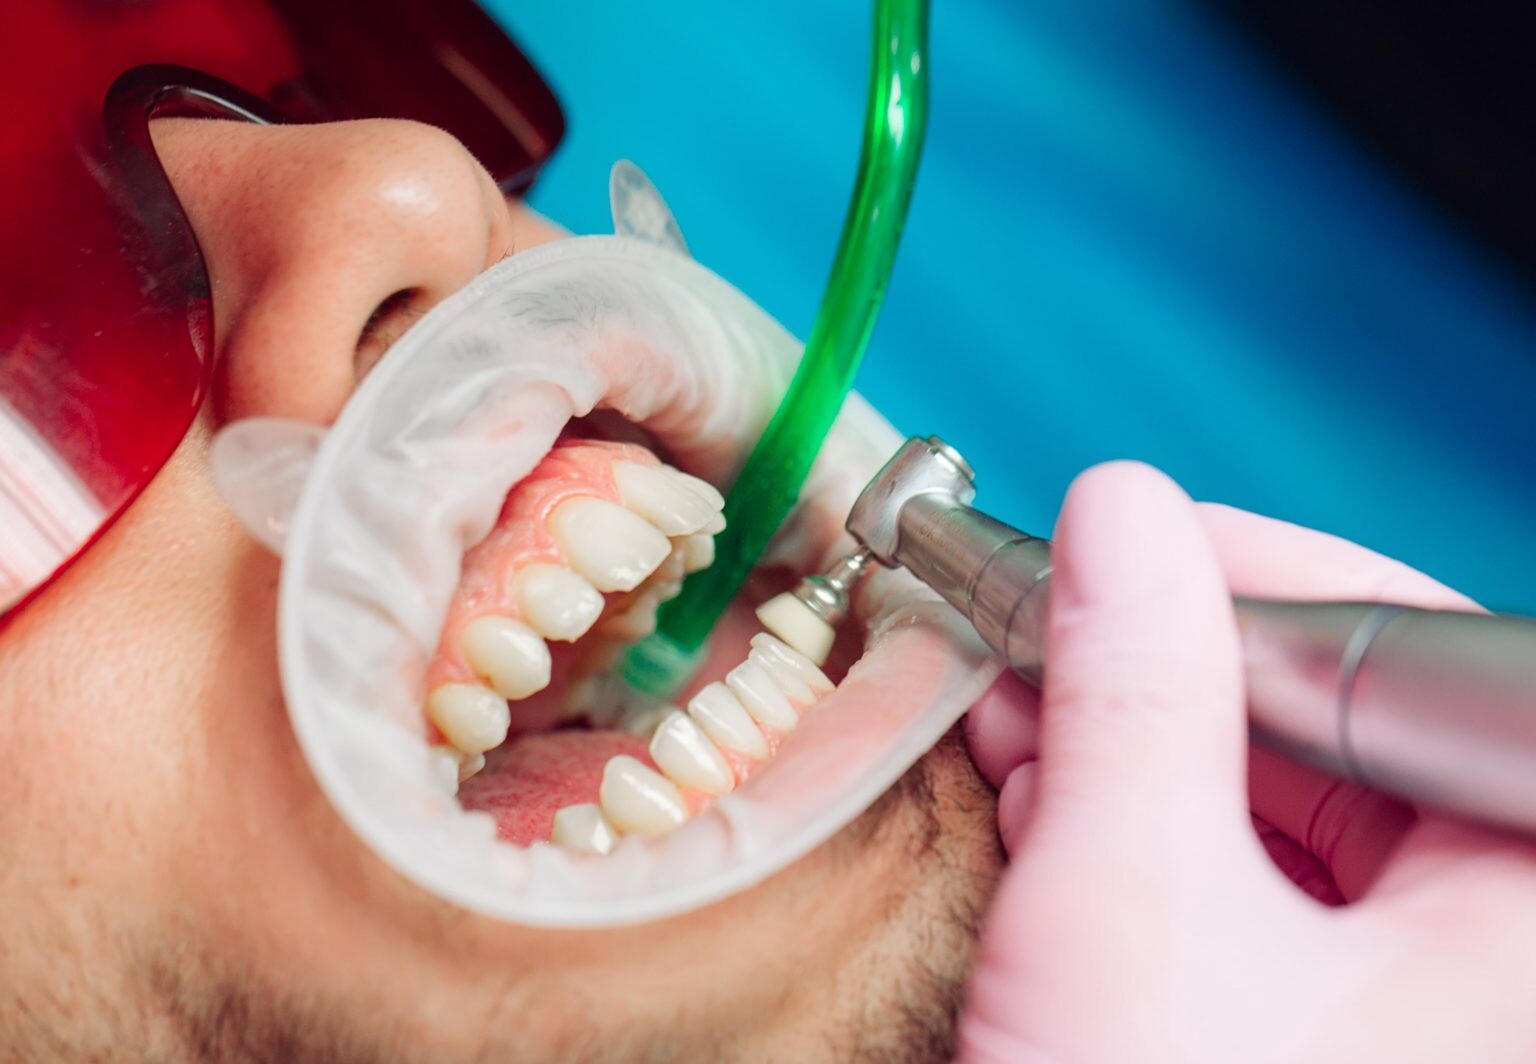

Regularly scheduled dental cleanings are crucial in keeping your teeth and gums healthy.

A prophylaxis treatment is a technical term for regular teeth cleaning. Prophylaxis appointments and proper at-home oral care can contribute to a radiant smile and overall well-being.

This article explores what dental cleaning entails, and what you can expect during a prophylaxis session.

Prophylaxis dental cleaning, is a preventive dental procedure to remove plaque, tartar, and stains from the teeth and gums.

Prophylaxis dental cleaning is an essential part of maintaining optimal oral health.

This procedure is typically performed by a dental hygienist or a dentist in a dental office.

What is Done During a Dental Prophylaxis Session?

A dental prophylaxis session usually involves several steps to ensure thorough cleaning of your teeth and gums.

During a teeth cleaning appointment, you can expect the following procedures:

Examination: The dental professional will comprehensively examine your mouth before the cleaning begins. This examination helps identify oral health issues and determine the appropriate treatment plan.

Plaque and Tartar Removal: Using specialized dental instruments, the dental hygienist or dentist will carefully remove plaque and tartar deposits from your teeth. They will focus on areas that are hard to reach during regular brushing and flossing.

Teeth Polishing: After plaque and tartar removal, the dental professional will polish your teeth using a rotating brush or a rubber cup with an abrasive paste. This step helps remove surface stains and leaves your teeth looking clean and shiny.

Flossing and Rinsing: Once the teeth are polished, they will floss between your teeth to remove any remaining debris or plaque. They may also ask you to rinse your mouth to remove any residual polishing paste or debris.